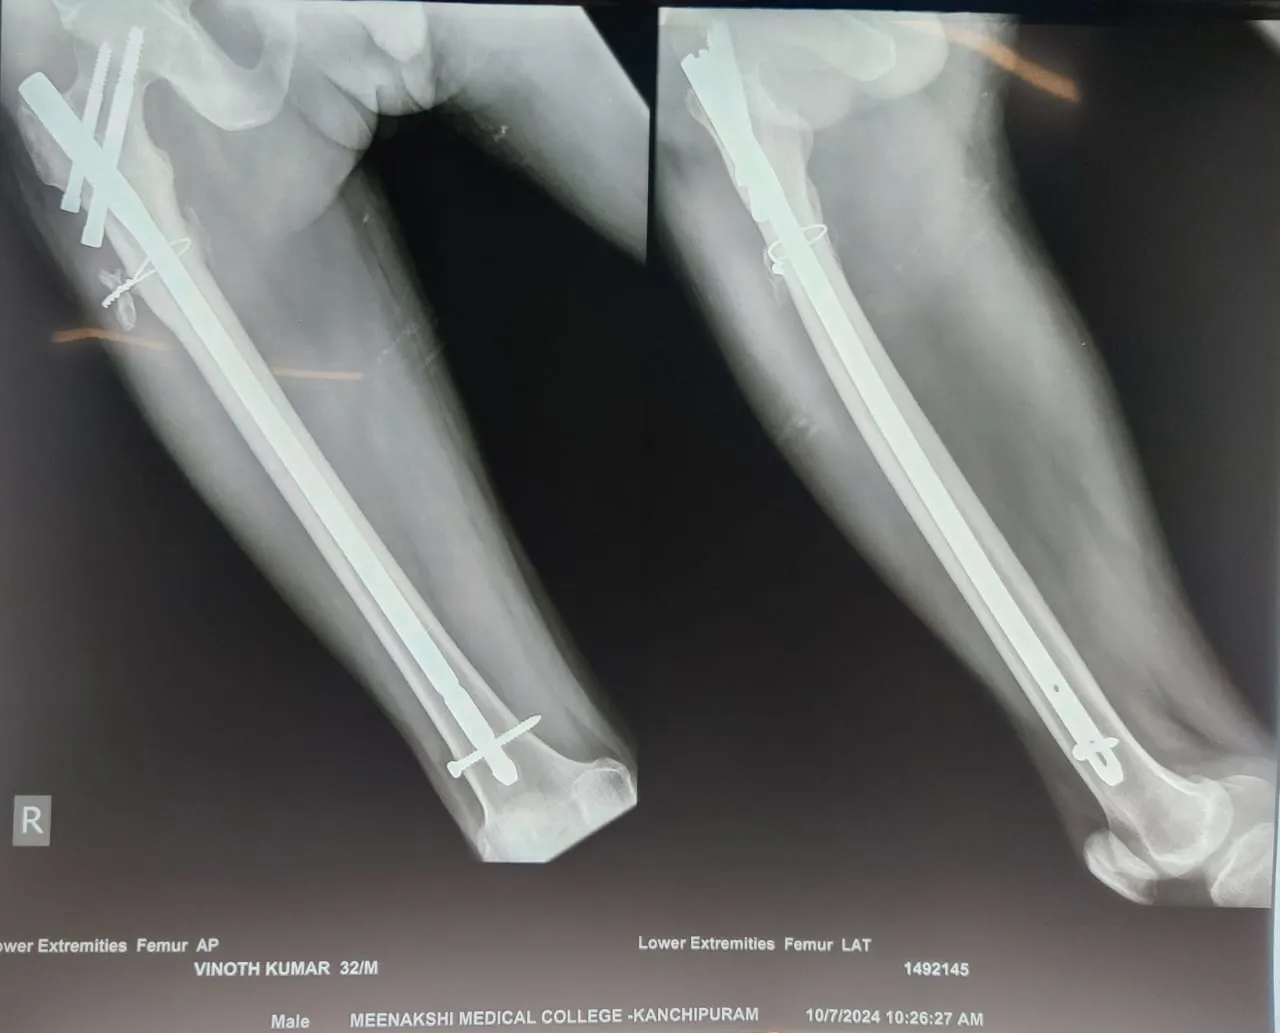

Dr.P.Sankaralingam M.S(ortho)., DNB (ortho).,MNAMS is an experienced senior consultant Orthopaedic surgeon who does about 350 joint replacement surgeries per year in addition to treatment of Trauma cases.

Standard Hospital, Chennai’s Centre of Excellence for Orthopaedics offers minimally invasive surgeries for faster recovery.

• Hip & Knee Replacement and Revision Surgeries

• All Trauma & Fracture Fixation (Nails, Plates, Non-union Repairs)